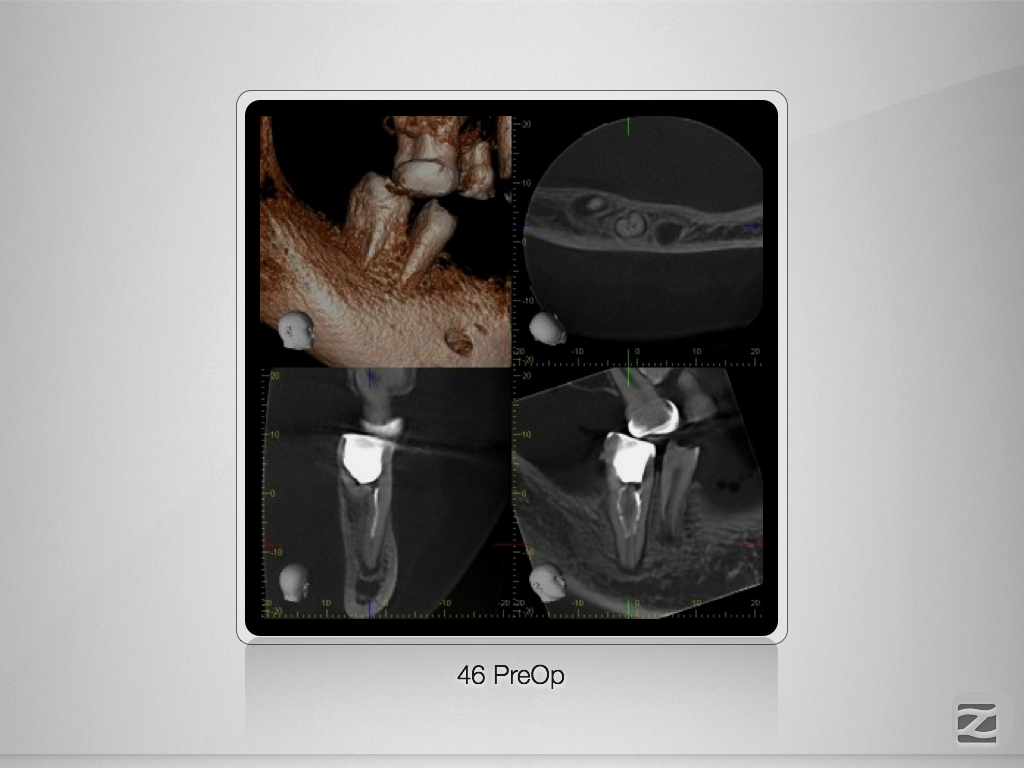

46D.005

Doppeltes C